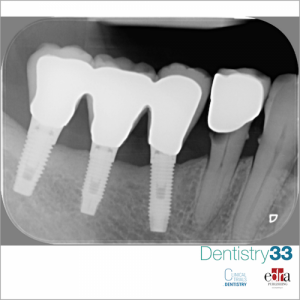

PURPOSE. To assess whether there are any clinical benefits to placing single dental implants either 0.5 or 1.5 mm subcrestally in healed bone crests.MATERIALS AND METHODS. Sixty partially edentulous...

Since the placement of dental implants is an increasingly frequent rehabilitation treatment, it is imperative to consider the possible complications. Surgical complications such as bleeding (24%) and...